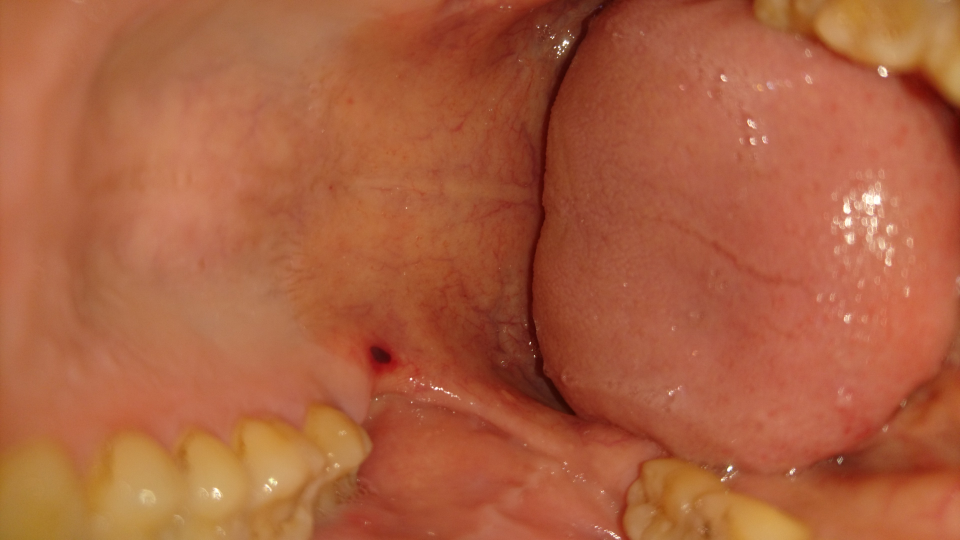

よろしくお願いします。 1月8日に左上顎奥に小さな血豆ができました。 気になりいじっていたら、潰してしまいました。 (写真あり) その後に、熱い飲み物(コーンスープ)を急いで飲んだところ、血豆が大きくなり慌てて血を出そうと押したところ、さらに大きくなってしまいました。 大きさは長さ3センチほどで、開口部分にまで広がってしまいました 病気 下の上に、血豆のようなものができました。 色は血豆のような、血が溜まったような感じで、 大きさは、直径1cmくらいです。 少し、染みる感じがします。 これは、ただの血豆や口2 口の中にできた血豆の治し方 21 潰さずに自然に治す 211 血豆が潰れてしまったら! 22 噛んで出来た時は冷やす;

写真あり 歯科受診後に口内を見たら頬内側に血豆 歯チャンネル歯科相談室